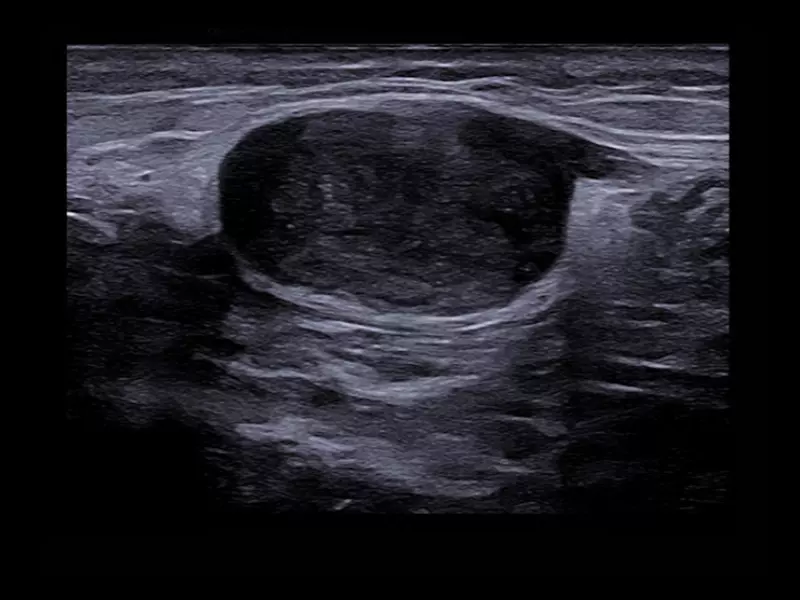

MyLab™9 Platform - High resolution imaging in testis

MyLab™9 Platform - High resolution imaging in testis